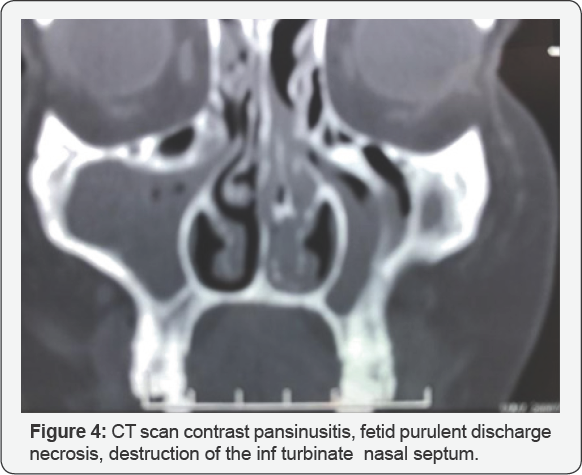

Infection (bacterial, fungal, or parasitic), Tuberculosis lupus, Leprosy, Leishmaniosis, Mucormycosis Rhinoscleroma. Inflammatory disease (Sarcoidosis, Wegener granulomatosis, Systemic Lupus Erythematosus, or Polyarteritis nodosa). Neoplastic processes (squamous or bas cell carcinoma, melanoma, esthesio neuroblastoma, adenoid cystic carcinoma, adenocarcinoma, fibrosarcoma, rhabdomyosarcoma, plasma cell myeloma, or an additional sinonasal lymphoma). Cocaine abuse, Trauma (gunshots, bites )with saddle nose deformity, mutilation giant cell granuloma, cholesterol granuloma and lobular capillary hemangioma, Non Hodgkin Lymphomas polymorphic reticulosis Figure 4.

vi. The diagnosis of mid facial NK/T-cell lymphoma is based on the histopathological picture, immunophenotype of the atypical cells and the analysis of T-cell receptor genes. The surface of the affected site is associated with crusting and necrotic tissue, so the diagnosis of NK/T-cell lymphoma is extremely difficult by taking only punch biopsy, excisional biopsy or deep biopsy is often essential for the diagnosis of this disease. The characteristic histopathological picture in NK/T cell lymphoma shows angiocentric and angiodestructive growth pattern with zonal necrosis. Immunohistochemical study shows positive CD3, CD43, CD45RO, CD20 and CD57 demonstrates the a typical lymphoid cells have T-cell phenotype. Radiological findings in CT scan and MRI are not distinctive for other malignant lesions, typically showing irregular margins, bone destruction and heterogenous contrast enhancement.